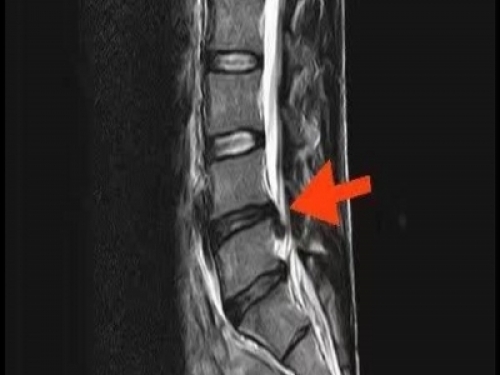

長期彎腰勞作容易患腰椎間盤突出,保守治療常見藥物有這些!

村裡的老王每天在田地裡勞作,為了一家人的生計,每天在田裡彎腰除草,照顧莊稼···但是這天去醫院體檢才發現自己居然患有腰椎間盤突出···

對於長期彎腰勞作的人來說,腰椎間盤突出症是常見病。因出現時間比較短,自然首選保守治療。